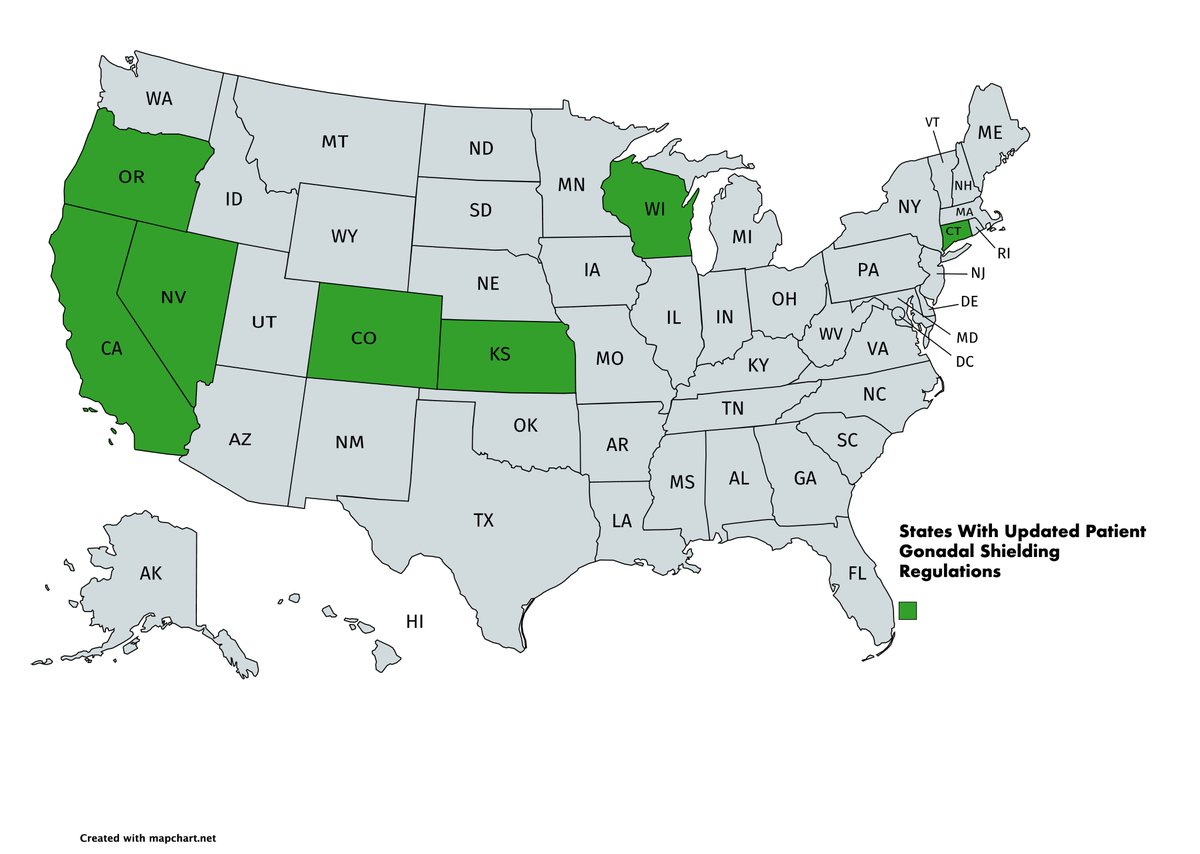

Kansas has become the latest state to allowing medical imaging facilities to choose not to use patient gonadal shielding. Will your state be next? American Association of Physicists in Medicine #ScienceBasedMedicine